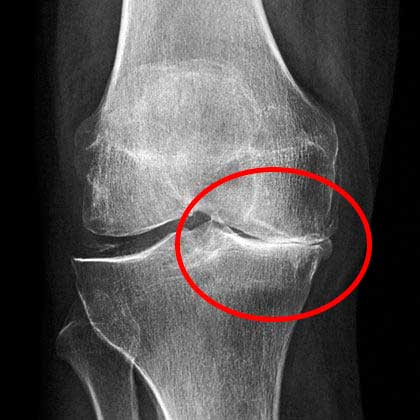

The condition of my knee at that time. Severe pain.

At the appointment, the doctor looked at the pictures for a long time and said that I should no longer do physical labor. And he forbade me to lift anything heavier than 2 kg.

X-rays showed serious problems with my knee.